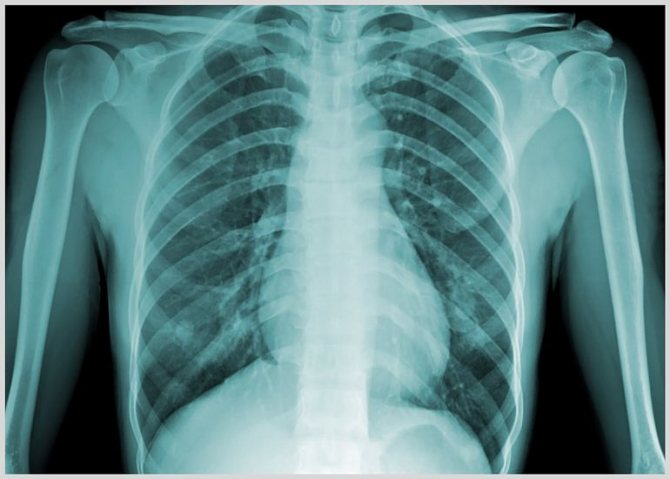

Пациенту, прежде всего, снимают ЭКГ и делают рентген органов грудной клетки. Дальнейшее обследование включает:

- рентгеновский снимок грудной клетки. Показывает наличие жидкостных элементов в легких. Показывает тотальное затемнение в центральных легочных отделах. При кардиогенном отекании затемнение может быть с обеих сторон, при одностороннем воспалении легких – затемнение с левой или правой стороны;

Диагностика

Для установки диагноза наиболее эффективным является рентген. Снимок помогает определить наличие недуга и стадию развития. При патологии картинка размыта, контуры нечеткие, околокорневые отделы имеют сниженную прозрачность.

При проведении рентгенологического обследования открывается следующая картина симптомов, которой характерно расширение корневой системы лёгких и отсутствие структурированности. Врач замечает расплывчатость картины лёгких, а также наличие линий Керли в сегментной структуре.

При прослушивании биения сердца не наблюдается его тон, что связано напрямую с шумным дыханием. При рентгенологическом обследовании наблюдается следующая картина:

- Рентген грудины. При проведении рентгена и наличии признаков расширения сердца и корней лёгких будет свидетельствовать о преобладании факторов наличия жидкости в лёгких.